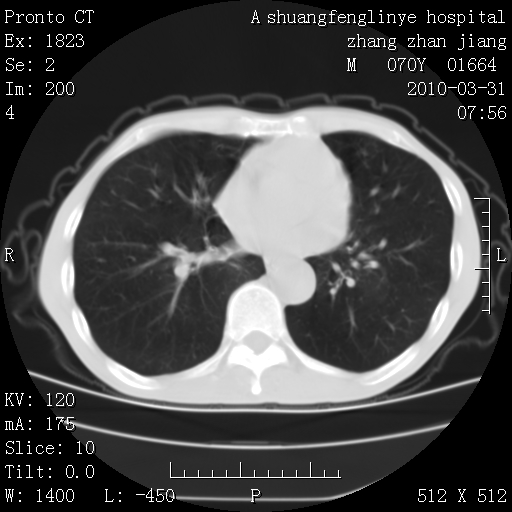

双上肺继发型tb并左上空洞形成,主动脉冠脉钙化。

支持:继发性肺结核伴空洞形成!建议纤支镜检查待出外周围型肺癌可能!

1)两肺上叶继发性肺结核并左肺上叶空洞形成。2)冠状动脉及主动脉钙化。